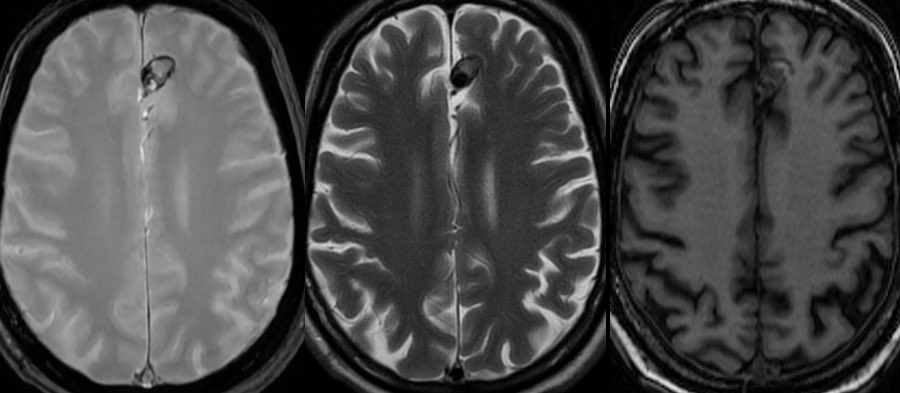

📢 Following the publication of the #BraTSAfrica dataset & with the upcoming #BraTS2025 Challenge, we’re taking the next step: 🧠 Help shape the Brain Tumor Imaging Protocol Africa Project (BTIP-Africa) 🎯 Goal: Co-create standard glioma imaging guidelines for African settings 📋 Take our 10-min survey ➡️ docs.google.com/forms/d/e/1FAI… 📄 BraTS-Africa paper: doi.org/10.1148/ryai.2… #GlobalHealth #Neuroimaging #Radiology #AIforGood @SARIMRadiologie @EEsrnm @GRadiologists @RadKenya @Radiology_SA @rigsudan @NigerianSIR @taraso_tz @RwandaMedicalAs